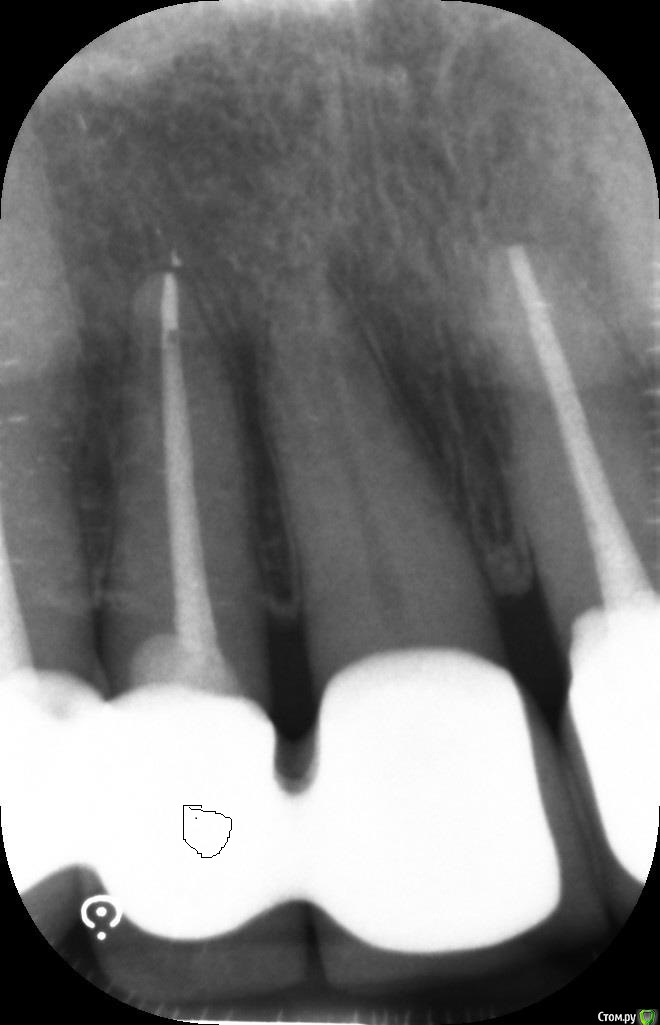

ellenchik Опубликовано 9 января, 2020 Автор Поделиться Опубликовано 9 января, 2020 Добрый день, уважаемые Доктора.Я снова к Вам за советом. После отпуска ( Перемена климата -прилетела из +25 в +2 град.) уже неделю болит уже другой передний зуб под коронкой (канал пролечен 4,5 г. назад) Болит очень высоко с внешней стороны десны в самом вверху. Особенно при нажатии точки прямо под правой ноздрёй носа. Боль жгучая,ноющая. С нёбной стороны никаких болевых ощущений. Временами такая "гуляющая" боль по передним верхним зубам. Врач сделал снимки и сказал, что надо делать резекцию верхушки корня у этого зуба и заодно у рядом стоящего зуба (по моему клык) с пролеченным каналом. Еще он где-то увидел трещину.В рот заглянул,но зубы ни на какие реакции не проверял. На снимках причинный зуб (по моим ощущениям ) с "кривым кружочком"Буду очень признательна за советы. Действительно все так плохо по снимкам и необходима резекция обоих зубов? Или есть другие варианты. И на каком зубе видна трещина? С уважанием ЕленаP.S-Прикрепляю на всякий случай старый снимок ( третий по счету ) этих зубов после лечения в 2015 г. Ссылка на комментарий

ellenchik Опубликовано 10 января, 2020 Автор Поделиться Опубликовано 10 января, 2020 Посмотрите ,пожалуйста снимки. Что можно по ним сказать?К кому лучше с этим обратиться, к хирургу или эндодонтисту?У меня еще и в понедельник 13.01 запланирована небольшая операция,отменить нельзя. (не с зубами связано) 1)Можно ли отложить лечение зуба на неделю?2). может пока Антибиотики? С уважением Елена Ссылка на комментарий

ellenchik Опубликовано 12 января, 2020 Автор Поделиться Опубликовано 12 января, 2020 Посмотрите ,пожалуйста снимки. Что можно по ним сказать?К кому лучше с этим обратиться, к хирургу или эндодонтисту?У меня еще и в понедельник 13.01 запланирована небольшая операция,отменить нельзя. (не с зубами связано) 1)Можно ли отложить лечение зуба на неделю?2). может пока Антибиотики? С уважением Елена Ссылка на комментарий

ellenchik Опубликовано 12 января, 2020 Автор Поделиться Опубликовано 12 января, 2020 Если мои снимки малоинформативны,подскажите плиииз... Сделаю новые.Но всё же надеюсь Ваши мнения по поводу резекции корней. Очень нужен компетентный взгляд со стороны. Может есть другие варианты и не так всё критично по снимку. Буду очень признательна. Ссылка на комментарий